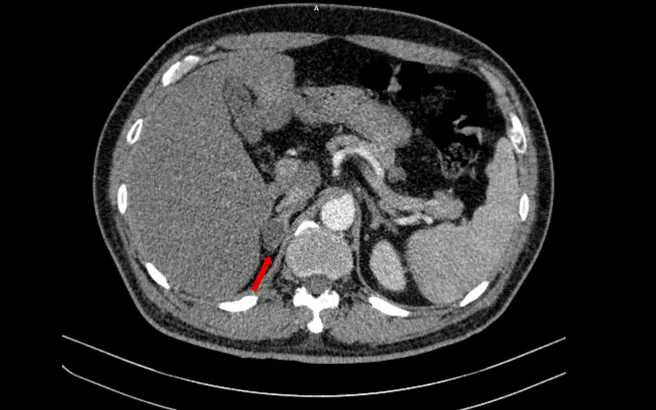

Người bệnh nhập viện vì tiểu khó kéo dài. Qua các kỹ thuật hiện đại như CT, MRI, xạ hình xương và PET/CT, bác sĩ phát hiện nhiều tổn thương tại phổi, tuyến tiền liệt, thượng thận và xương. Thách thức lớn nhất là xác định đây là ung thư nguyên phát hay di căn.

Kết quả sinh thiết và hóa mô miễn dịch cho thấy hai khối u có nguồn gốc hoàn toàn khác nhau: ung thư biểu mô tuyến phổi và ung thư tuyến tiền liệt điểm Gleason 9, thuộc nhóm nguy cơ cao.